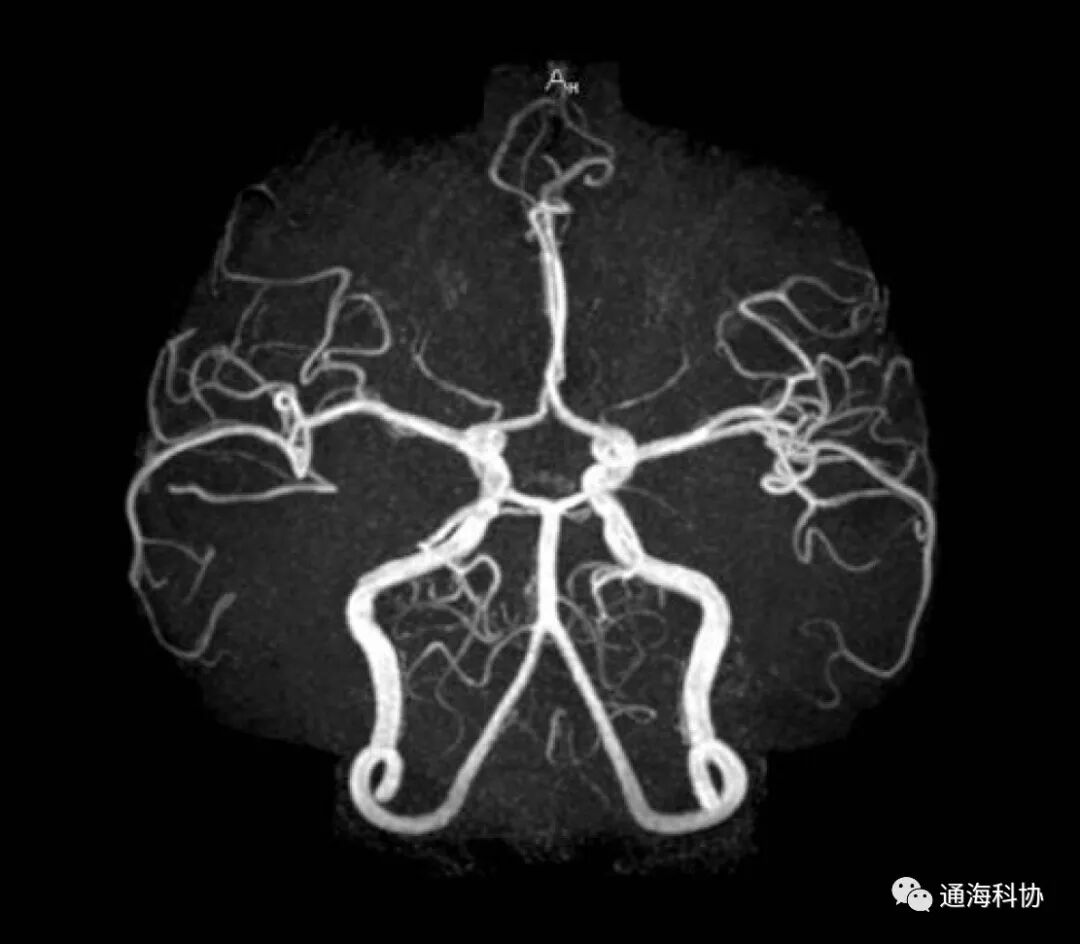

核磁共振成像检查又称自旋成像,也称磁共振成像,是英文Magnetic Resonance Imaging的译意,简称MRI。核磁共振成像是从原子层面,通过外加梯度磁场检测其物理变化,而绘制出来物体内部结构图像,是一个很复杂的过程,作为科普就不讲得那么深了。

平常情况下,每个水分子的磁场磁力线方向是随机的,当在核磁共振强大的磁场作用下,这些水分子的磁场磁力线会呈现出一致性,当磁场消失,这些水分子磁力线又会恢复随机状态。核磁共振就是通过发出磁场和停止磁场的交替过程,收集人体磁场磁力线变化数据,通过计算机复杂的运算,重建成像。

磁共振设备主要由三大基本构件组成,即:磁体部分,由主磁体(产生强大的静磁场)、补偿线圈(校正线圈)、射频线圈和梯度线圈组成;磁共振波谱仪部分,主要包括射频发射部分和一套磁共振信号的接收系统组成;数据处理和图像重建部分,由信号变换器、暂存器、图像处理机、控制台、显示器等组成。

核磁共振所采用的磁场是很强的,一般在1.5T~3T之间。T(特斯拉)是磁场的很高的磁场强度单位,1T等于10000Gs(高斯),而地球磁场赤道只有0.3Gs,南北极有0.6Gs,最强的铷磁铁磁场强度也只有300Gs,因此,核磁共振的磁场强度是地球约50000倍,是最强磁铁的100倍。

对早期诊断敏感,在一些病变早期时就能够显示出异常,能够早于CT和B超等方法发现问题,比较适宜对头颅、脊髓、骨骼、四肢等检查,如头部检查,由于没有骨骼伪影的影响,因此对颅底、椎管检查效果尤其好。相对CT还弥补了其不能直接多平面成像的缺陷,不需要注射造影剂就能够形成血管造影,对病灶显示的更为清晰。